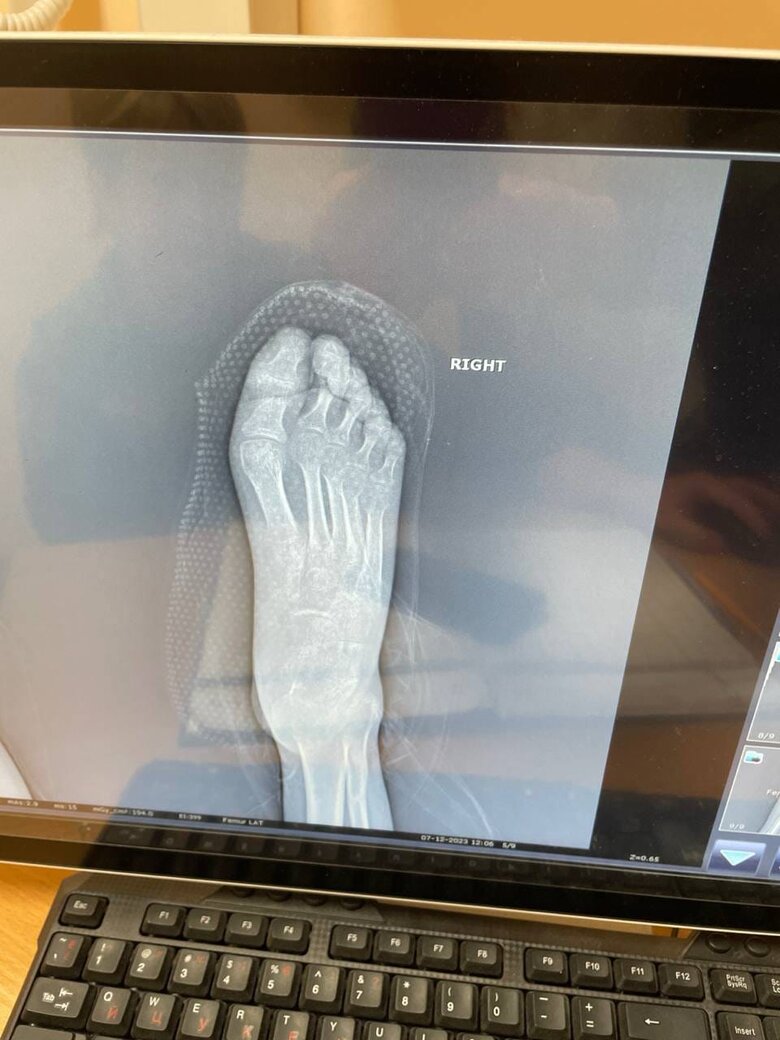

Друзі, знайомтеся: це Алік. Мій боєць, сапер, який отримав важкі поранення влітку минулого року під час штурмової операції південніше Бахмуту. Операція пішла невдало, групу накрили гради. Алік врятував кількох поранених бійців, надавав їм першу допомогу, але й сам зазнав серйозних ушкоджень.

Військовий третьої штурмової бригади Алік